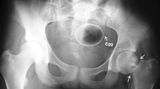

Die Webseite radiopaedia.org zeigt, welche Dinge Ärzte auf Röntgenbildern schon entdeckt haben. Die Aufnahmen wirken skurril und erschreckend zugleich und machen deutlich, wie weit die eingeführten Dinge bereits in den mescnhlichen Darm vordringen können.

Aber Glück im Unglück für die Patienten: Die Gegenstände können meist ohne Operation entfernt werden. Sehen Sie hier einige der spektakulärsten Röntgenaufnahmen. Da runzeln selbst Chirurgen die Stirn.